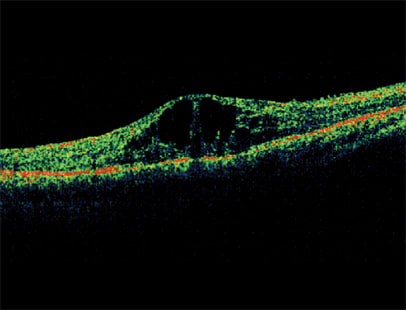

OCT showing diabetic macular edema (DME)

Of current interest are a number of recent therapies for AMD that are being investigated in cases of DR complicated by diabetic macular edema (DME). These include intravitreal injections of anti-VEGF factors and steroids.